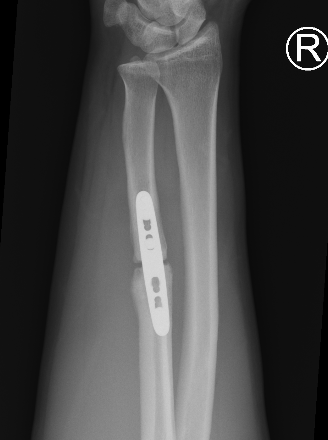

Operative management

Indications

Acute fractures

- > 50% displacement

- > 10 degrees angulation

Compression plating